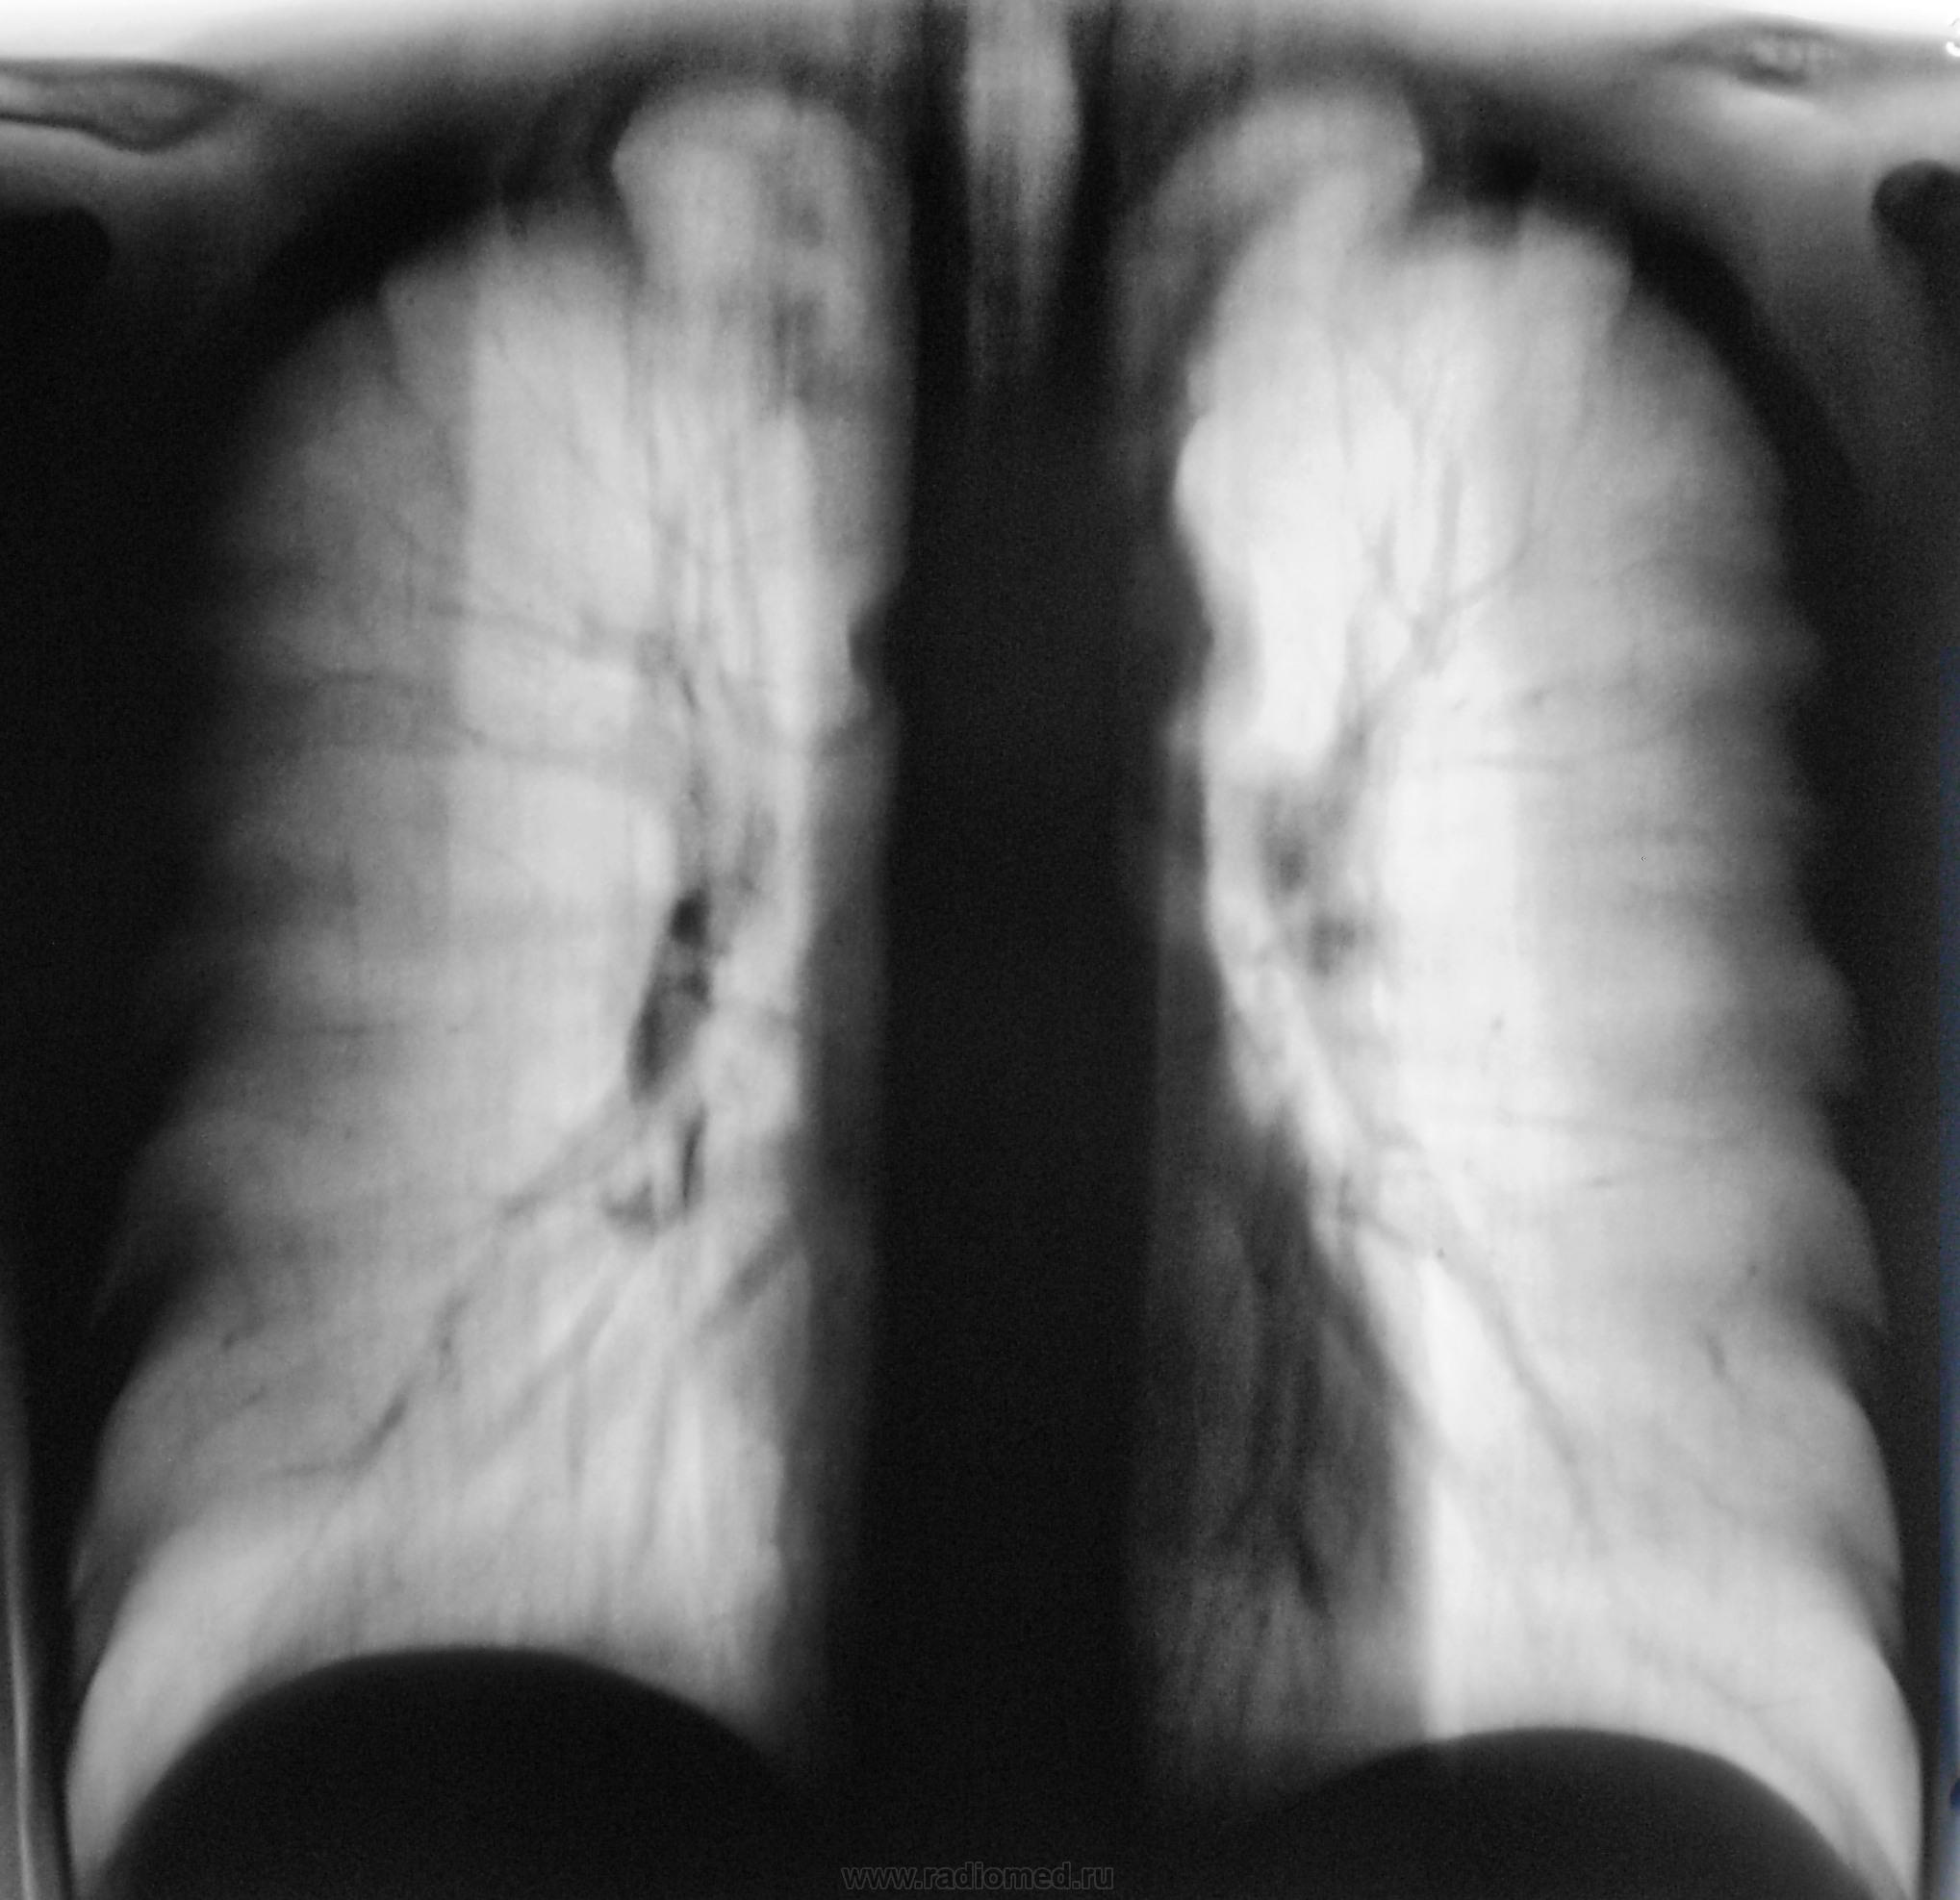

Да, именно мужчина, отлично сложенный, с хорошо развитыми мышцами, занимается спортом.

Да, у меня, как правило, "танец" начинается с верхушек.

Дело в том, что этого пациента я зацепил еще год тому назад.

Снимки ниже.

Снимки.